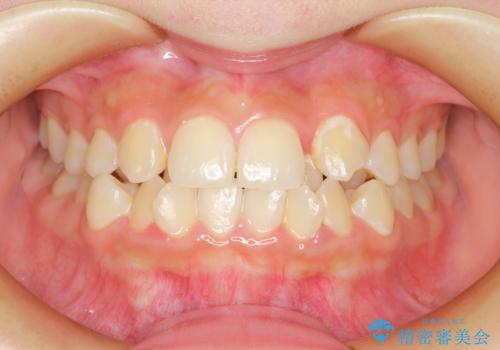

前歯の突出を防ぎながらガタつきを解消。上下左右4番抜歯による審美ワイヤー矯正

担当医 河口智英